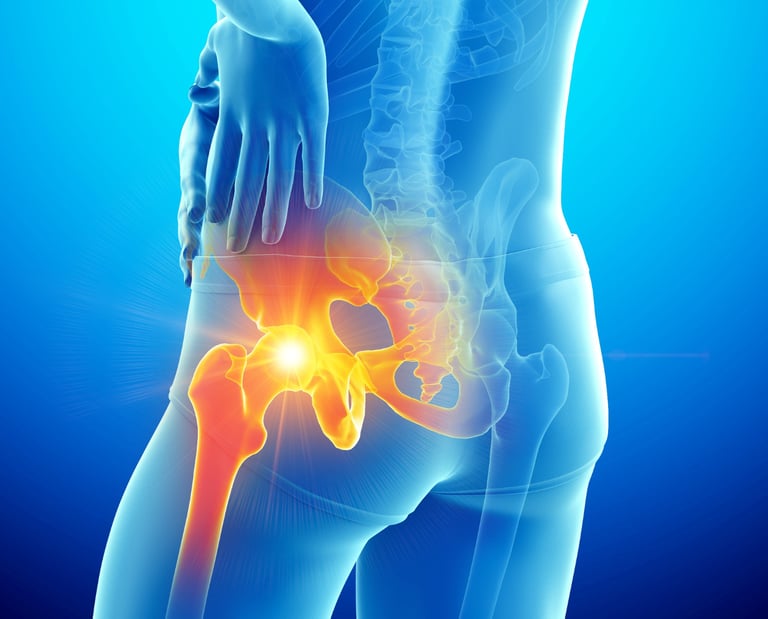

Η οστεοπόρωση είναι μια πάθηση που χαρακτηρίζεται από αδυναμία των οστών, κάνοντάς τα πιο επιρρεπή σε κατάγματα. Είναι πιο συχνή στις γυναίκες μετά την εμμηνόπαυση, αλλά μπορεί να επηρεάσει και τους άντρες. Μέσω σωστής διατροφής, άσκησης και φαρμακευτικής αγωγής, μπορεί να προληφθεί ή να ελεγχθεί. Η πρώιμη διάγνωση είναι κρίσιμη για την αποφυγή σοβαρών καταγμάτων και τη διατήρηση της ποιότητας ζωής.

Οστεοπόρωση